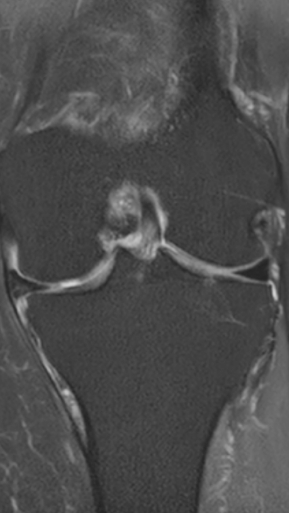

Рецидивирующий синовит коленного сустава

Излечение за 1 процедуру ФДТ РЕВИКСАН

Параметры изменяются в зависимости от процедуры

Дата публикации: 11.02.2026 10:52:38